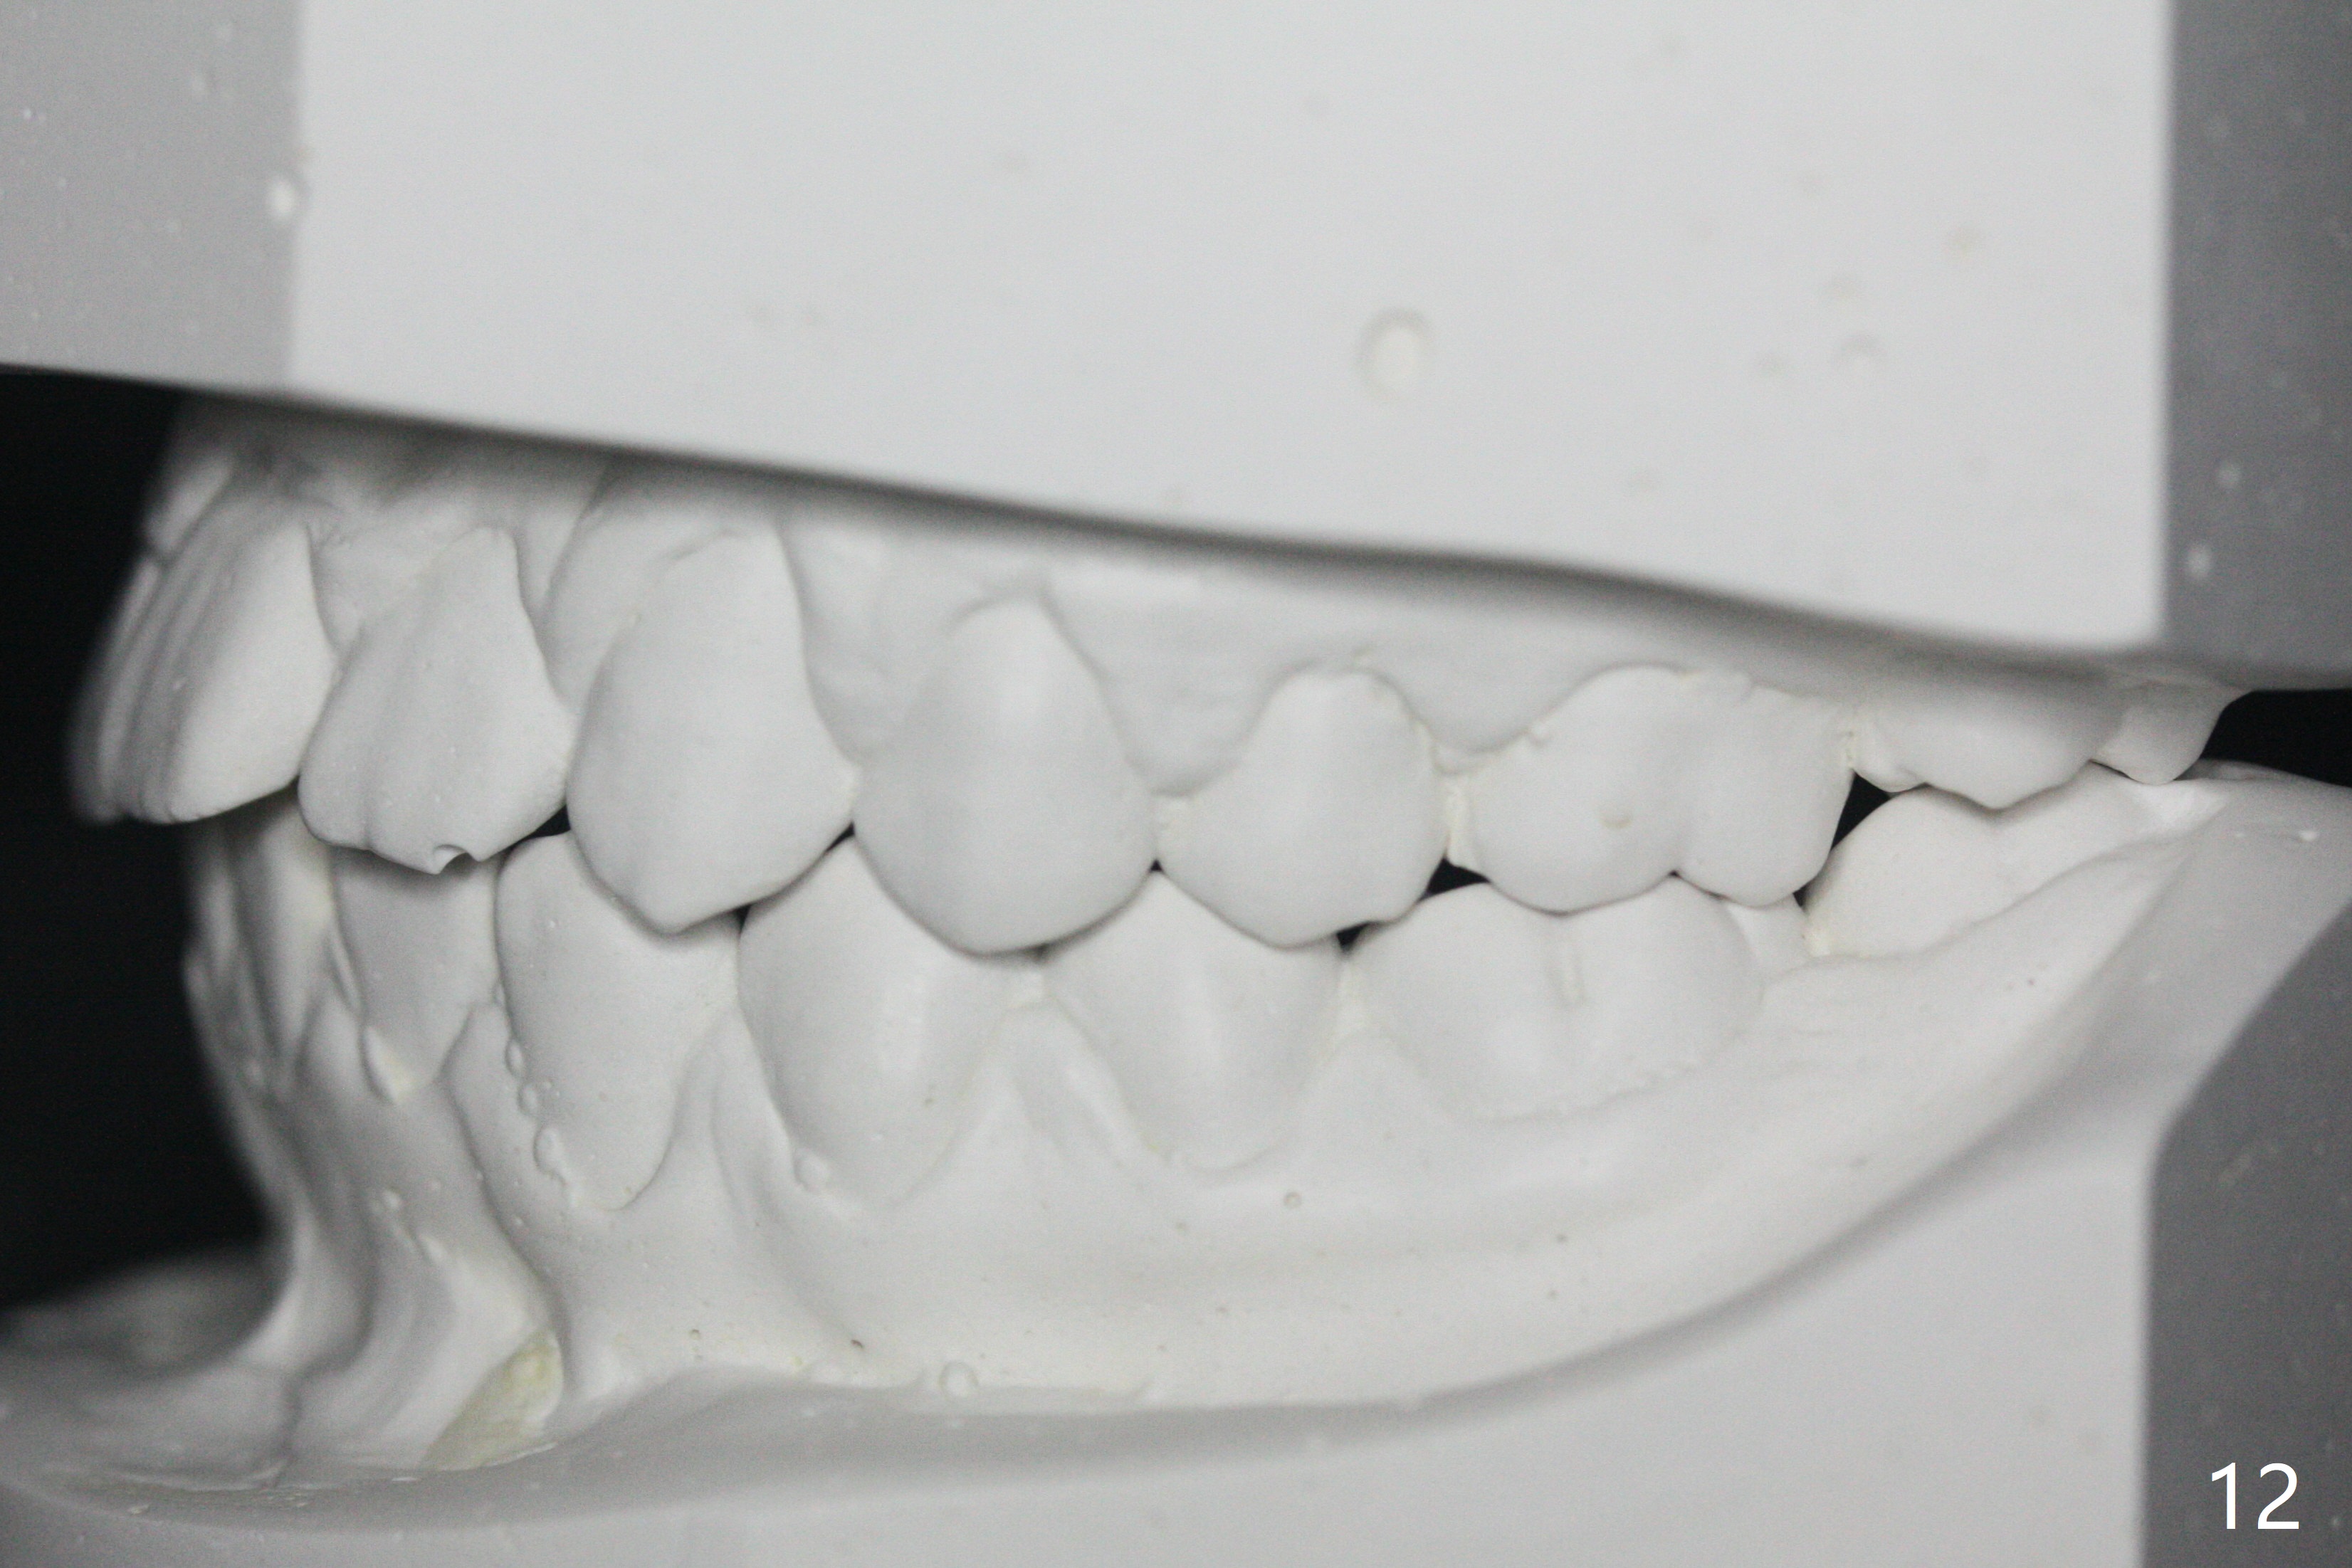

A 14-year-old woman, used to be a dental phobic (Fig.13), agrees with orthodontic treatment. Her mother is concerned about UL1 protrusion (Fig.8,11) and decalcification (Fig.8 *) and UR4 cross bite (Fig.7,10,14). There is mild lip constraint (Fig.1,3), as related to light dental protrusion (Fig.2,4), although the upper dental midline is not deviated (Fig.2). History shows that UR3 erupts before UR D is extracted, which is associated with UR4 cross bite. After arch expansion, consider proximal reduction to reduce anterior overjet if present. In fact that latter is not done; instead Class II is conducted.